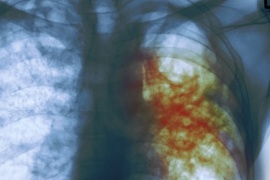

Recomendaciones de la OMS en la lucha contra la tuberculosis

La Organización Mundial de la Salud ( OMS ) ha hecho públicas nuevas orientaciones para mejorar el tratamiento de la tuberculosis multirresistente, para la que recomienda tratamientos exclusivamente orales, que son más eficaces y tienen menos probabilidades de producir efectos colaterales  adversos. Conocé la situación en nuestra provincia